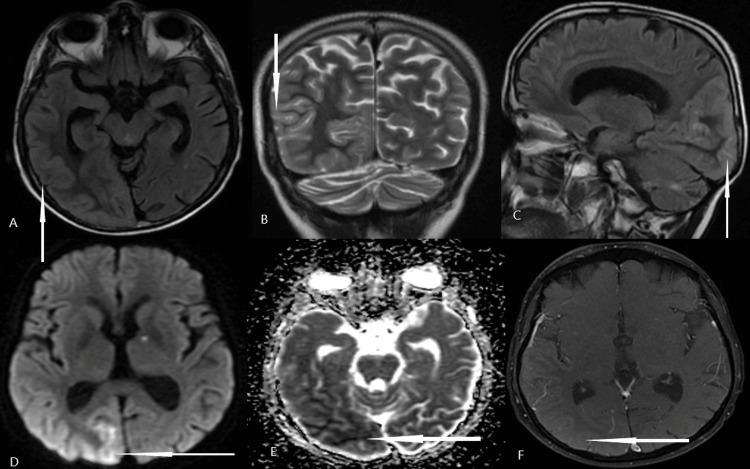

Stroke-like migraine attacks after radiation therapy (SMART) syndrome is a rare and delayed complication of brain irradiation involving impaired cerebrovascular autoregulation, and diagnosis is based on distinct clinic-radiographic findings and exclusion of differentials. We report a 38-year-old man, who received cranial irradiation 28 years before and developed episodes of headache and visual aura, followed by left hemianopia, aphasia, behavioral disturbances, and focal seizures. An MRI of the brain revealed gyral swelling with restricted diffusion and mild contrast enhancement over the right temporoparietal and occipital region, and fludeoxyglucose-FDG PET scan showed hyperperfusion in the corresponding brain region. He improved completely with pulse steroids and antiseizure medications. The recognition of this syndrome is important as we can reassure patients and their families and help avoid unnecessary and invasive diagnostic tests.

摘要